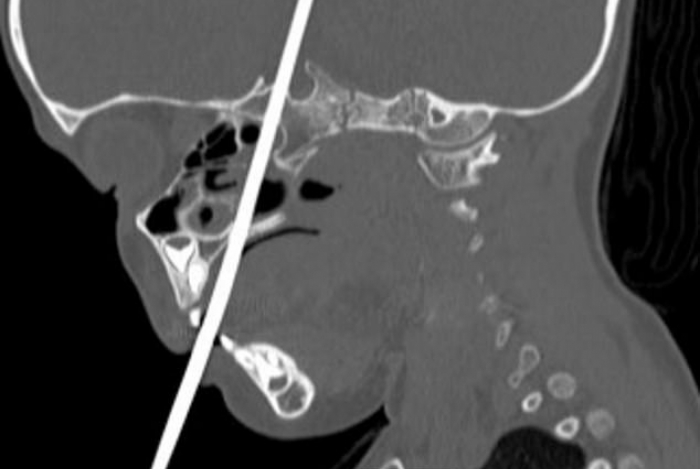

Uma criança de três anos teve a cabeça perfurada por uma agulha de tricô enquanto brincava que era uma fada. Ela estava pulando em cima de uma cama quando se desequilibrou e caiu. O objeto entrou pela boca da menina, perfurou o crânio e atingiu o cérebro.

Ela foi levada às pressas ao hospital, que fica em Utah, nos Estados Unidos, e os médicos descobriram que a agulha atingiu a hipófise e o hipotálamo, regiões responsáveis por hormônios e pela coordenação dos movimentos do corpo. Por mais que ela estivesse sangrando muito, uma tomografia mostrou que os pequenos vasos sanguíneos dela estavam a salvo.